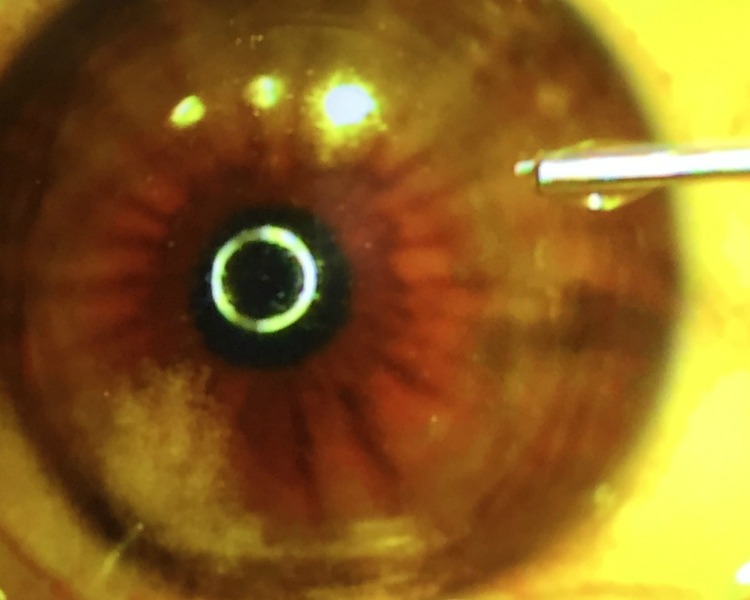

Meanwhile, my mother/chauffeur/caretaker/photographer took pictures of the whole thing while I was having the procedure. While I’ll admit it took me a few days to really look at these, it does show almost every part of the procedure – one shot at a time.

So here’s your disclaimer: if you want to see some really, up close photos of my procedure, be my guest. If your stomach is a little weak, I wouldn’t do it. Just remember, these photos are in no order of the procedure, but they are pretty wild what happens in the Lasik Suite. However, if you want to see a video that explains exactly what happens in a procedure like this, then take a look at this.